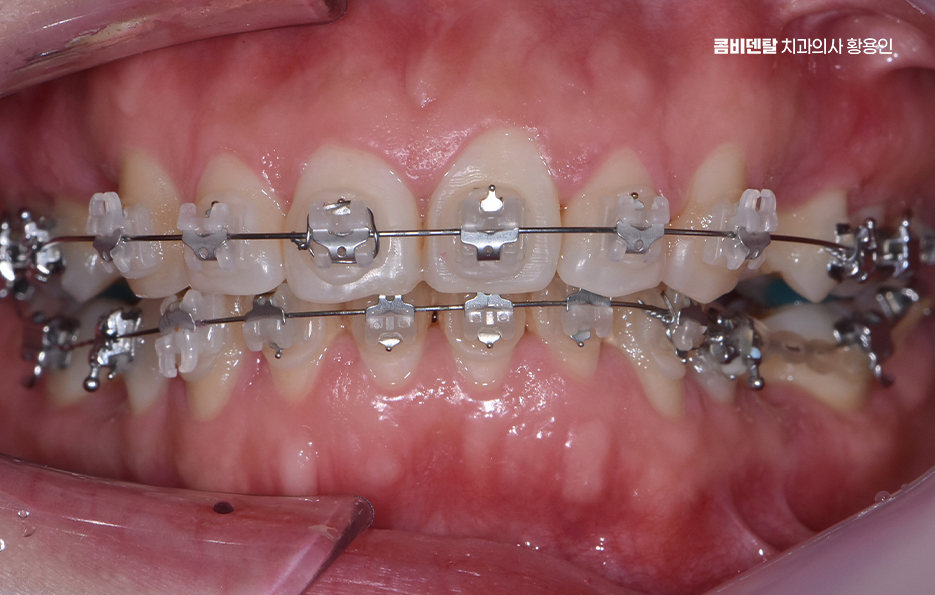

돌출입 팔자주름 교정 치아를 어떻게 움직이느냐에 따라 얼굴 인상이 달라지는 것인데 돌출입 교정은 일반적으로 소구치 네 개를 발치한 후, 앞니를 뒤쪽으로 밀어넣고 악궁을 재배열하는 방식으로 진행되며 앞니가 뒤로 이동하고 자연스럽게 입술이 들어가게 되고, 입술 돌출도가 줄어들면서 얼굴이 전반적으로 부드럽고 조화로운 느낌으로 바뀔 수 있어요

옆모습에서 입이 덜 나와 보이고, 턱선이 또렷해지는 것도 이런 원리에서 비롯되며 치아 배열 자체는 물론이고, 입술과 턱 근육의 균형이 맞춰지기 때문에 얼굴 인상이 부드럽고 안정적으로 바뀌는 거예요.

돌출입 팔자주름 교정 그럼 팔자주름은 어떻게 변하느냐는 질문도 많은데 돌출입이 있는 사람들은 입 주변 근육에 지속적으로 긴장이 들어가기 때문에 팔자주름이 더 도드라져 보이는 경우가 많고 입술이 앞으로 나와 있다 보니, 코 밑에서부터 입꼬리로 이어지는 주름이 더 깊게 파이고, 표정이 굳어 보일 수도 있었어요.

그런데 치아를 뒤로 이동시키면서 입술이 안쪽으로 정리되면, 입 주변의 긴장도 줄어들게 되고, 자연스럽게 팔자주름이 완화되는 효과가 생기는 것이며 물론 주름 자체를 없애는 시술처럼 극적인 효과는 아니지만, 돌출이 줄어들면서 팔자주름이 덜 도드라져 보이고 얼굴의 입체감이 개선되는 건 분명한 변화라고 볼 수 있어요